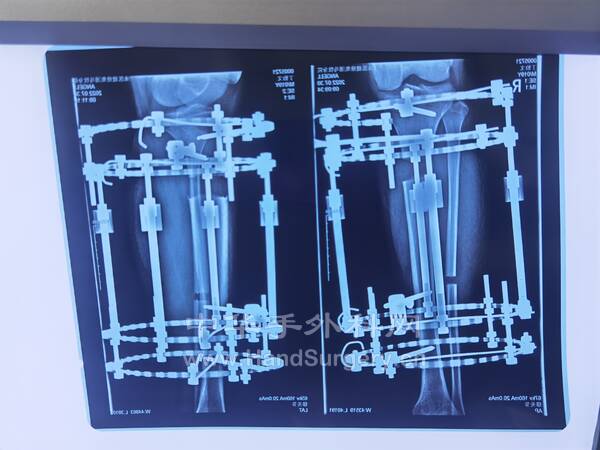

3.胫骨延长外固定架术后根据患者情况决定每日拧1圈/2圈,拧3天停1天,1个月复查DR,最终延长的长度以患者行走的舒适度为准!延长的长度约3.5--6cm,外固定架需佩戴4-6个月(图4--7)4.第一,四跖骨短缩的儿童如果想改善外观,可行截骨延长外固定架固定术,需单侧做,时间4-6个月(图8-9)

Ilizarov外固定架治疗马蹄内翻足畸形的模型(图1--17)

明日需要手术的右足马蹄外翻足,扁平足小患者资料(图18--41)

明日需要手术的右足马蹄外翻足,扁平足小患者资料(图1-24)